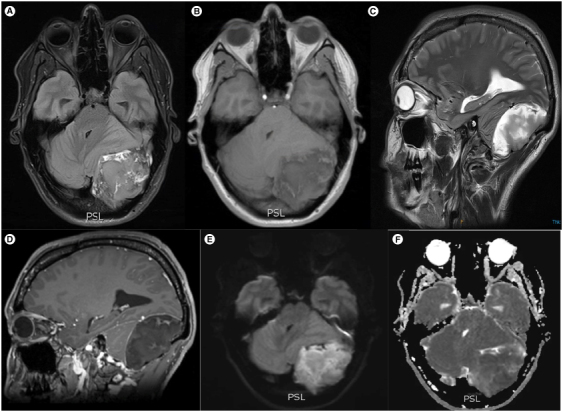

表皮样囊肿并不常见,在所有颅内肿瘤中占比不到 1%。其中,后窝巨大蝶鞍内表皮样囊肿(即超过5厘米的囊肿)更为罕见。在此,我们报告了对一名累及枕骨的 7 厘米后窝表皮样囊肿的完全切除,患者是一名 32 岁女性,头痛和眩晕由急性转为慢性加重。包括囊壁在内的完整切除对于防止复发和恶变至关重要。我们报告了迄今为止第一篇系统性综述,评估了 25 例后窝巨大表皮样囊肿病例,讨论了其表现、临床和影像学特征以及明确的治疗策略,为有限的现有数据增添了新的内容。

Epidermoid cysts are uncommon accounting for less than 1% of all intracranial tumors. Among them, giant intradiploic epidermoid cysts of the posterior fossa i.e. those exceeding 5 cm are an even rarer entity. Here we report on the complete resection of a 7 cm posterior fossa epidermoid cyst involving the occipital bone in a 32-year-old female presenting with an acute on chronic exacerbation of headaches and vertigo. Complete resection including the cyst wall is crucial in preventing recurrence and malignant transformation. We add to limited existing data by reporting on the first systematic review to date assessing 25 cases of giant epidermoid cysts of the posterior fossa to discuss presentation, clinical and radiographic features and definitive management strategies.